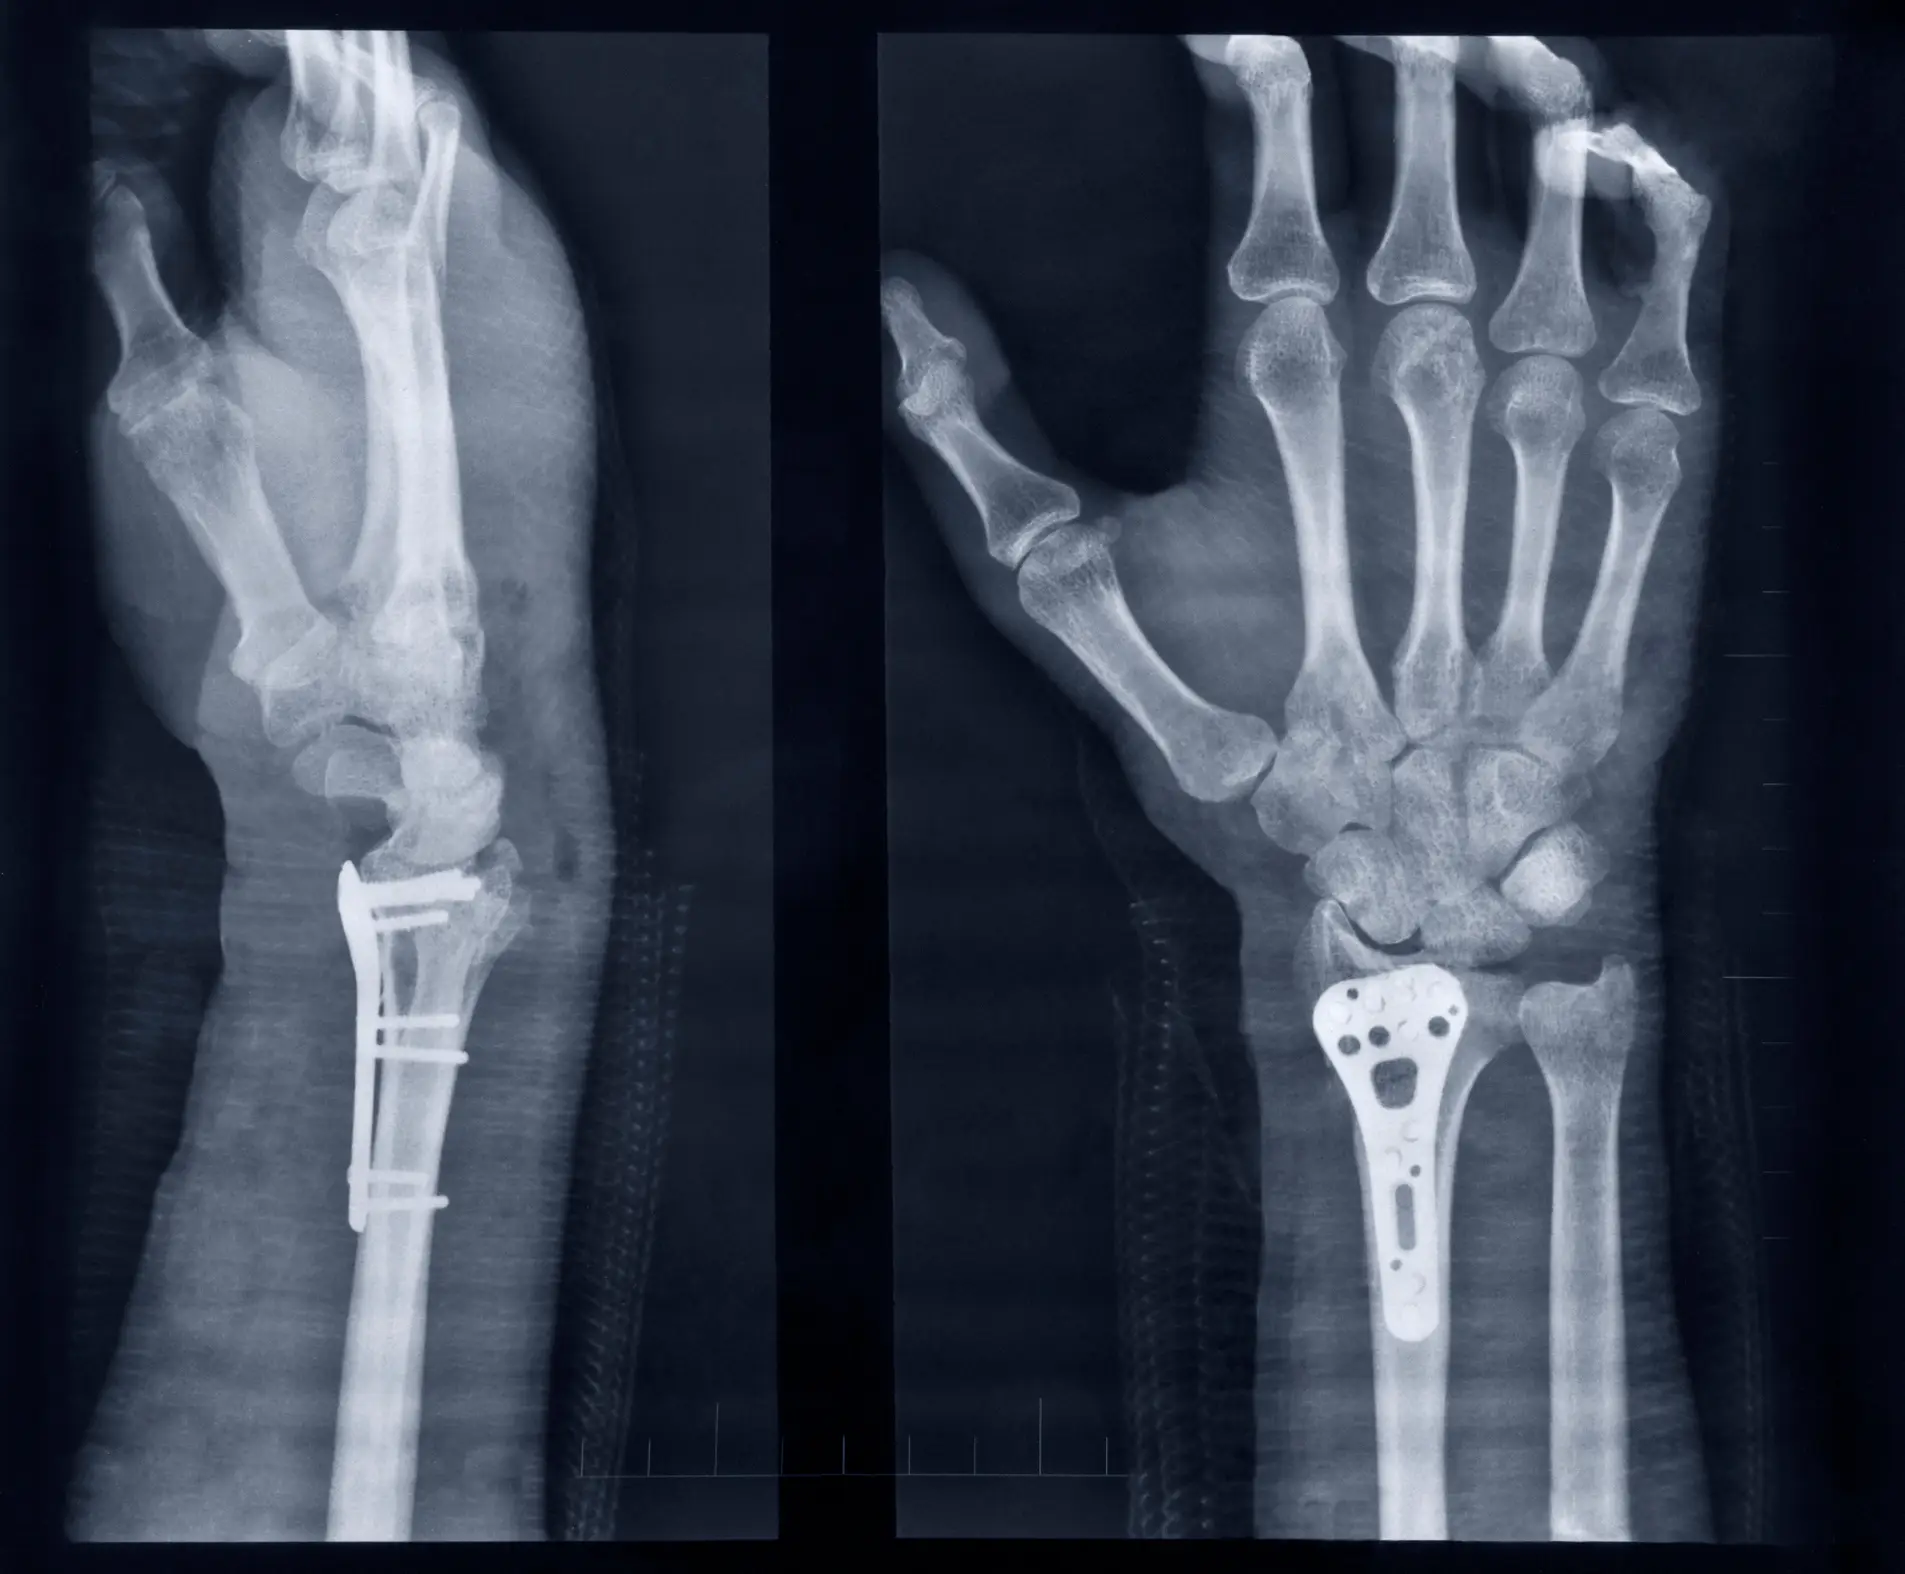

Some need to be treated internally, with devices like plates, rods and screws holding the bones in place while they heal.

In one trial, doctors used Bone-02 to repair repair a severe wrist fracture in under three minutes.

After just three months of recovery, the patientâs fracture had healed without complications and they had full use of their wrist once more.